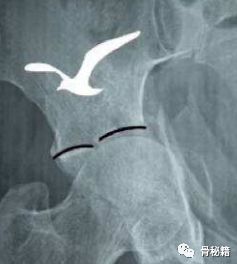

红色为压缩后,绿色为压缩前。

这种臼顶的压缩还有个特殊的名字叫海欧征,髋臼匹配度出现了问题,这个时候就需要注意有臼顶压缩了。